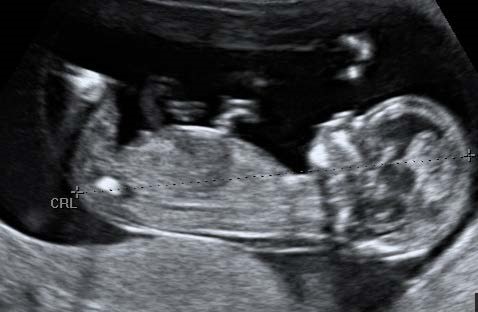

Criteria for measurement of the fetal crown rump length (CRL) as part of the combined 1st trimester screening programme

The CRL range should be between 45.0 and 84.0 mm.

The magnification of the fetus should be as large as possible clearly demonstrating the entire crown-rump length.

A midline sagittal section of the whole fetus should be obtained with the fetus horizontal on the screen, either supine or prone. The fetus should be in a neutral position with fluid visible between the fetal chin and chest, neither hyper extended nor flexed.

The best of three measurements should be taken. Linear callipers should be used to measure the maximum un-flexed length. Intersection of the callipers (+) should be placed on the outer margin of the skin borders of the CRL. Two images of the measured CRL must be retained, one for the patient record and one for audit purposes.